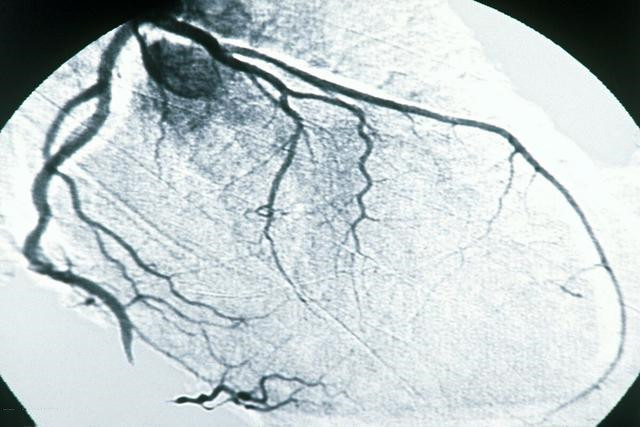

做了造影显示:右侧血管狭窄75%,左前方血管方狭窄60%,左后方血管狭窄95%,在左后方血管就是旋支放了一枚支架。放完支架,过了两三天,让患者多走几步试试看,在医生观察下,患者快走也不犯病了,自己上五楼也不会发作胸痛了。